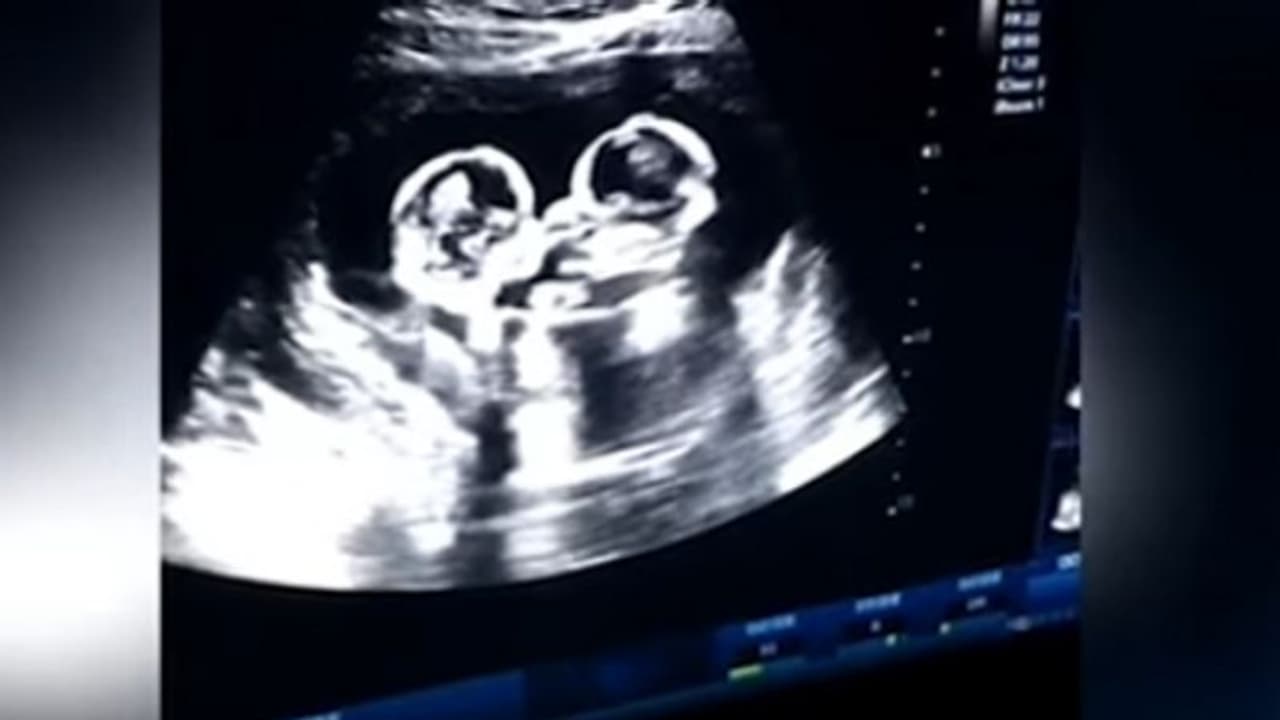

சீனாவை சேர்ந்த பெண் ஒருவர் நிறை மாத கர்ப்பிணியாக இருந்த நிலையில், அவரின் கருவில் உள்ள குழந்தைகளின் ஆரோக்கியத்தை பரிசோதனை செய்வதற்காக மருத்துவர் ஸ்கேன் செய்துள்ளார்.

அப்போது தாயின் வயிற்றில், இருந்த இரட்டை குழந்தைகள் ஒன்றோடு ஒன்று, அன்பாக சண்டையிட்டுள்ளது. இதனைக் கண்ட மருத்துவர் இன்ப அதிர்ச்சியில் உறைந்தார். மேலும் இந்த காட்சியைப் பதிவு செய்து இக்குழந்தையின் பெற்றோருக்கும் காட்டியுள்ளார்.